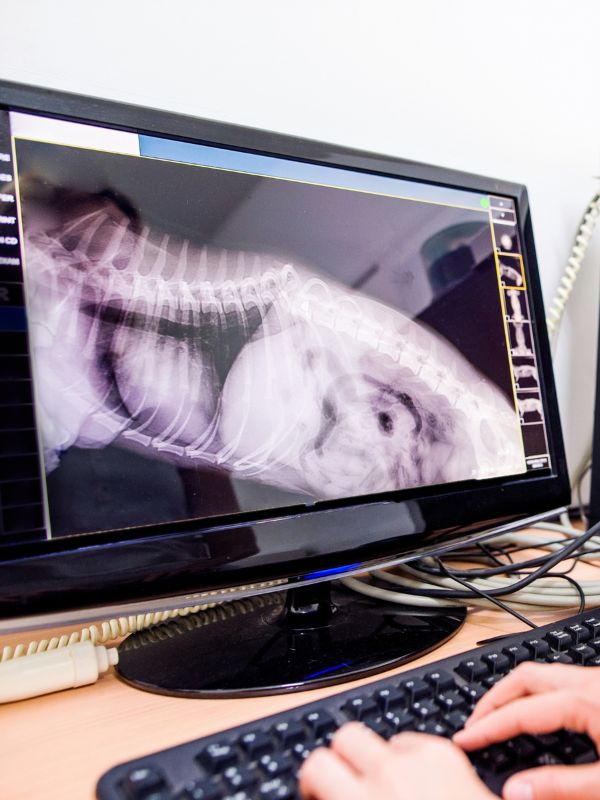

Digital Radiology

Digital radiography (DR) is an advanced form of X-ray that produces a 2-dimensional digital radiographic image instantly on a computer. This technique uses X-ray sensitive plates to capture data during object examination, which is immediately transferred to a computer.

By offering this service, it allows our veterinary team to view the images that assist in diagnosis and start treatment promptly.